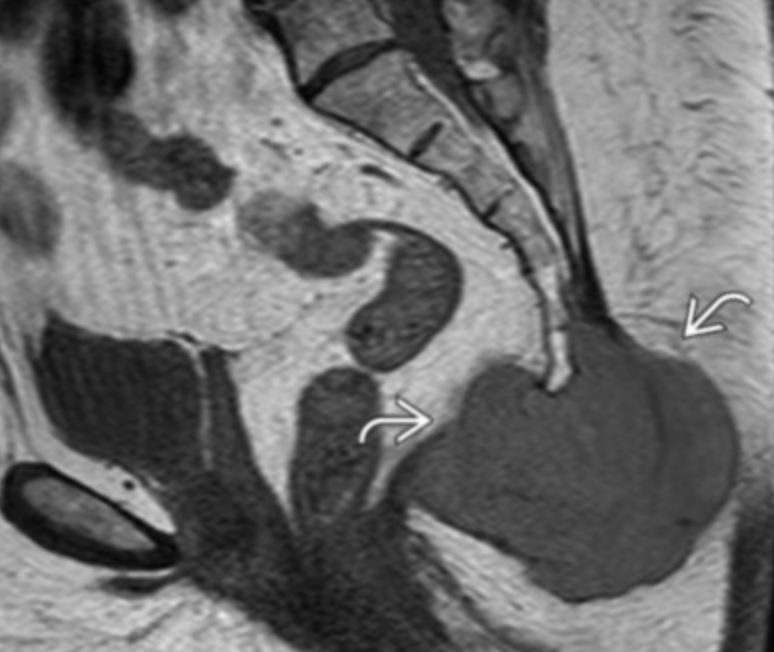

Sacrococcygeal teratoma

• Usually identified by 5th week of gestation

• Not really seen after neonate period (not expected in kids >1 year or even a few months tbh)

• Typical teratoma look with cystic and mixed density